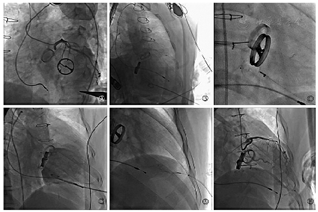

2019年9月10日,手术在介入手术室进行,患者取仰卧位,全身麻醉后行气管插管机械辅助通气,同时经食管超声心动图辅助术中影像学评估及全程监测心包及胸腔。术前经胸超声心动图提示:心包粘连,心动周期内左心室前壁、心尖处与胸廓位置相对固定。穿刺右侧股动脉置入6F短鞘,泥鳅导丝引导4.0左冠状动脉导管逆行至左冠状动脉开口,分别在前后位、左前斜45°、右前斜38°、足位26°进行左冠状动脉选择性造影,明确心尖无冠状动脉血管区域,同时借助X线下直头镊辅助定位,最终确定经皮穿刺进针点为左侧腋前线第5肋间(图2)。行经皮心尖穿刺,置入5F短鞘,鞘管头部放置于左心室中间。调整C臂至右前斜38°、足位26°使二尖瓣机械瓣为一个平面且左心房、左心室展开,经短鞘送入5F猪尾导管行左心室造影,提示:二尖瓣机械瓣瓣周漏,心脏收缩期反流血液迅速充盈左心房。随后,撤出5F猪尾导管,使用2.6米直头泥鳅导丝引导5F单弯导管进入左心室内,探过瓣周漏口进入左心房使单弯导管盘成圈,撤出泥鳅导丝置换为预弯头部的Amplatzer Ultrastiff加硬导丝进入左心房内打圈。撤出单弯导管及短鞘,沿加硬导丝送入COOK 5F 90 cm外周长鞘跨过瓣周漏口进入左心房,撤出加硬导丝。结合术前影像学测量,选择6 mm ADO-Ⅱ封堵器送入,X线下精准定位于瓣周漏口并展开。推拉试验证明封堵器定位牢固,X线下显示无卡瓣现象。遂释放封堵器,置换猪尾导管行术后左心室造影,结果提示:封堵器位置良好,瓣周反流消失。经食管超声心动图同样证实封堵器位置良好,二尖瓣机械瓣叶活动良好,瓣周反流消失。经外周长鞘送入第2枚6 mm ADO-Ⅱ封堵器,回撤长鞘时将封堵器紧贴左心室壁释放封堵穿刺针道,X线及超声心动图双重明确封堵器一端紧贴于心室游离壁,一端于心肌外,遂释放封堵器。术后经食管超声心动图证实无心包积液,胸腔积液。术后即刻,患者苏醒并撤除呼吸机,转至心脏重症监护室观察。3天后,复查超声心动图提示瓣周反流消失、心包、胸腔无积液,患者平稳出院。

Ⓐ选择性左冠状动脉造影明确心尖无冠状动脉区域 Ⓑ经心尖左心室造影 Ⓒ顺行释放封堵器封堵瓣周漏口 Ⓓ封堵后左心室造影 Ⓔ封堵心尖穿刺针道 Ⓕ术后选择性左冠状动脉造影